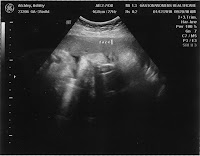

The doctor did my tummy check and the heart rate was good and strong on the doppler (150's). He measured my tummy and then the fun began. She, of course, has now decided to measure small again. This happened before (in November) and the ultrasound proved that she was fine and in the 50th percentile for growth...just laying low. Well, they went ahead and did an ultrasound while we were there, and Lillian is in the 17th percentile for her weight/growth. This is a bit concerning because at the 10th percentile, that is when they diagnose you with intrauterine growth restriction(which in layman's terms means the baby is small). If she doesn't start growing like she should, and we get to this diagnosis, then they may go ahead and deliver because it can be better for the baby to go ahead and be on the outside at that point. So...what we learned from the ultrasound is that Lillian is small...but she still looks good (and she is still a girl - yes, I had her check again just to be sure since the nursery has been painted in various shades of lilac and lavender to match her bedding). She was moving good, stretching, and her heart was beating strong. Other reassuring factors were that her placenta still looked good, the amniotic fluid levels looked good, and the bloodflow to the cord looked good. So...there is nothing wrong structurally that would be causing her to have growth problems. They have scheduled me for a non-stress test this Thursday morning so we will be able to see Lillian's activity level and her heart rate associated with it. If her heart beats faster when she moves (lasting at least 15 seconds) at least two times during a 20 minute period, then everything will be considered normal. If this doesn't happen, then the test will be considered abnormal, and they may do some further testing. After this test on Thursday, I will be going back to the doctor for the next two Tuesday mornings for both an ultrasound and another non-stress test to monitor Lillian's growth, activity, and ability to thrive.

Here are some pictures from the ultrasound....

Lillian's ear

Lillian was pouting in this one and her fingers are on her forehead

The white stuff is hair on her head.

Lillian's face

She may be small, but she has really big feet

Her second toe is half an inch long